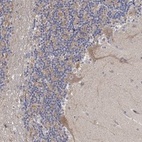

Immunohistochemical staining of human cerebellum shows moderate cytoplasmic positivity in Purkinje cells.